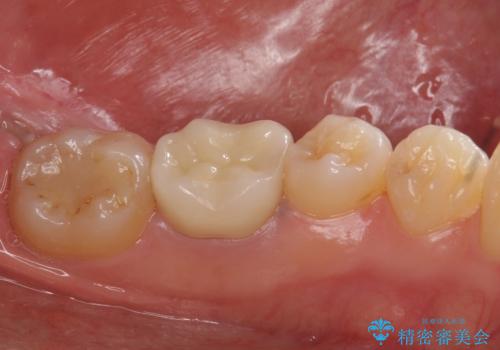

下の奥歯は口を開くと簡単に外から見えてしまいます。

銀色だった歯が白くなったことで大変喜んでいただけました。